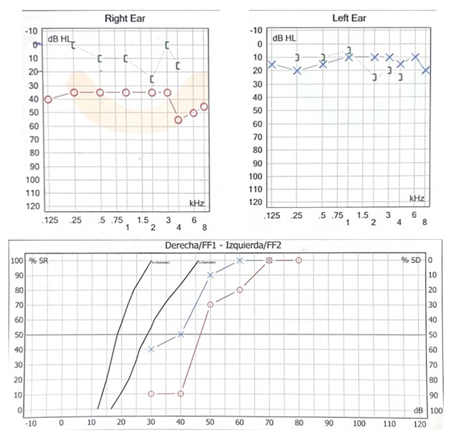

Se realiza tomografía computarizada simple de oídos donde se observa en oído derecho conducto auditivo externo ocupado en su tercio medio por lesión isodensa a hueso, de 8.54 x 8.65 mm, redonda, pediculada de origen en pared anterior, de bordes regulares, sin remodelación ósea, con presencia de material isodenso a tejidos blandos periférico a la lesión, sugestivo de cerumen; oído contralateral sin alteraciones. (Figura 2). Se realizó una audiometría tonal prequirúrgica (Figura 3, 4).

|

| (Figura 3). Audiometría tonal en oído derecho PTA 63.3 GAP 45: Hipoacusia conductiva moderada. | (Figura 4). Audiometría tonal en oído izquierdo PTA 17.85: Normoacusia. |

La paciente fue sometida a una resección quirúrgica por abordaje retroauricular, la lesión se encontraba limitada a la pared anterior del CAE coincidiendo con los hallazgos radiológicos preoperatorios. Se realizó una incisión retroauricular 1 cm por detrás del pliegue retroauricular, con hoja de bisturí #15 se diseca por planos hasta llegar a músculo auricular posterior, el cual se corta y se identifica mediante palpación pared superior e inferior del conducto auditivo externo, se realiza colgajo de Palva y se identifica espina de Henle, área cribosa y sutura timpanomastoidea, se accede a través de dicho colgajo a la piel de la pared posterior del CAE en la cual se realiza incisión cefalocaudal de 1 cm para lograr una exposición completa del CAE y se sostiene el colgajo utilizando un separador dentado. Se visualiza lesión y se elevan colgajos epiteliales superior e inferior al borde más lateral de la lesión, exponiendo de esta manera la cortical de la lesión. Con drill quirúrgico se fresa desde el centro de la lesión hasta quedar únicamente la cortical, obteniendo un “cascarón de huevo”, posteriormente se observa el pedículo de la lesión y se fractura, retirando por completo la lesión ósea, y se fresa la base de la lesión para evitar recurrencia. Posterior a la resección quirúrgica se realiza aseo del CAE, con antibiótico y esteroide, extrayendo restos celulares y se comprueba integridad de la membrana timpánica, se feruliza con Silastic y gelfoam impregnado con corticoide y antibiótico. La paciente presentó una adecuada evolución audiológica corroborada por audiometría tonal, la cual demostró normoacusia en el oído intervenido. Durante las citas postquirúrgicas se evidenció una adecuada cicatrización de tejidos retroauriculares así como los colgajos epiteliales del conducto. La evolución quirúrgica fue favorable, al mes se encontraba asintomática y la audiometría de control reporta normoacusia bilateral. (Figura 5).

| (Figura 5). Audiometría con normoacusia bilateral. |